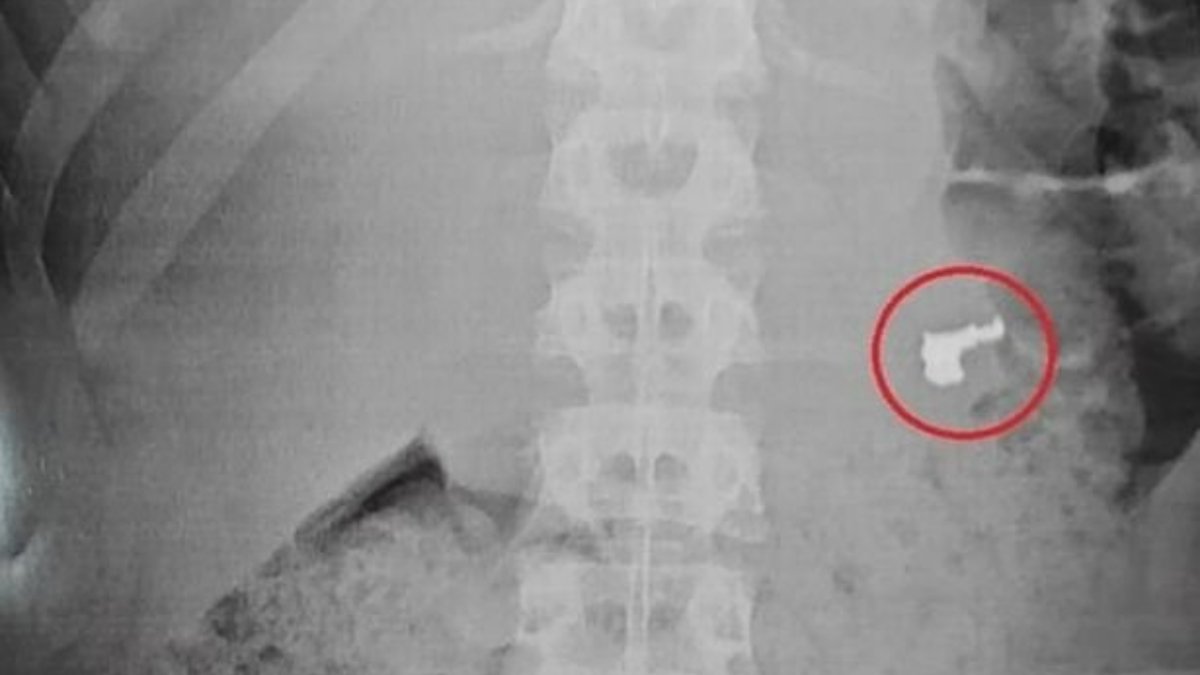

Bununla birlikte, tıbbi muayene yani röntgen esnasında şaşırtıcı bir durum ortaya çıktı. Zanlılardan birinin midesinde altın bir zincir bulundu. Gencin yaptığı hırsızlığın ardından yakalanmamak için kolyeyi yutması ise hastanedekiler tarafından şaşkınlıkla karşılandı.